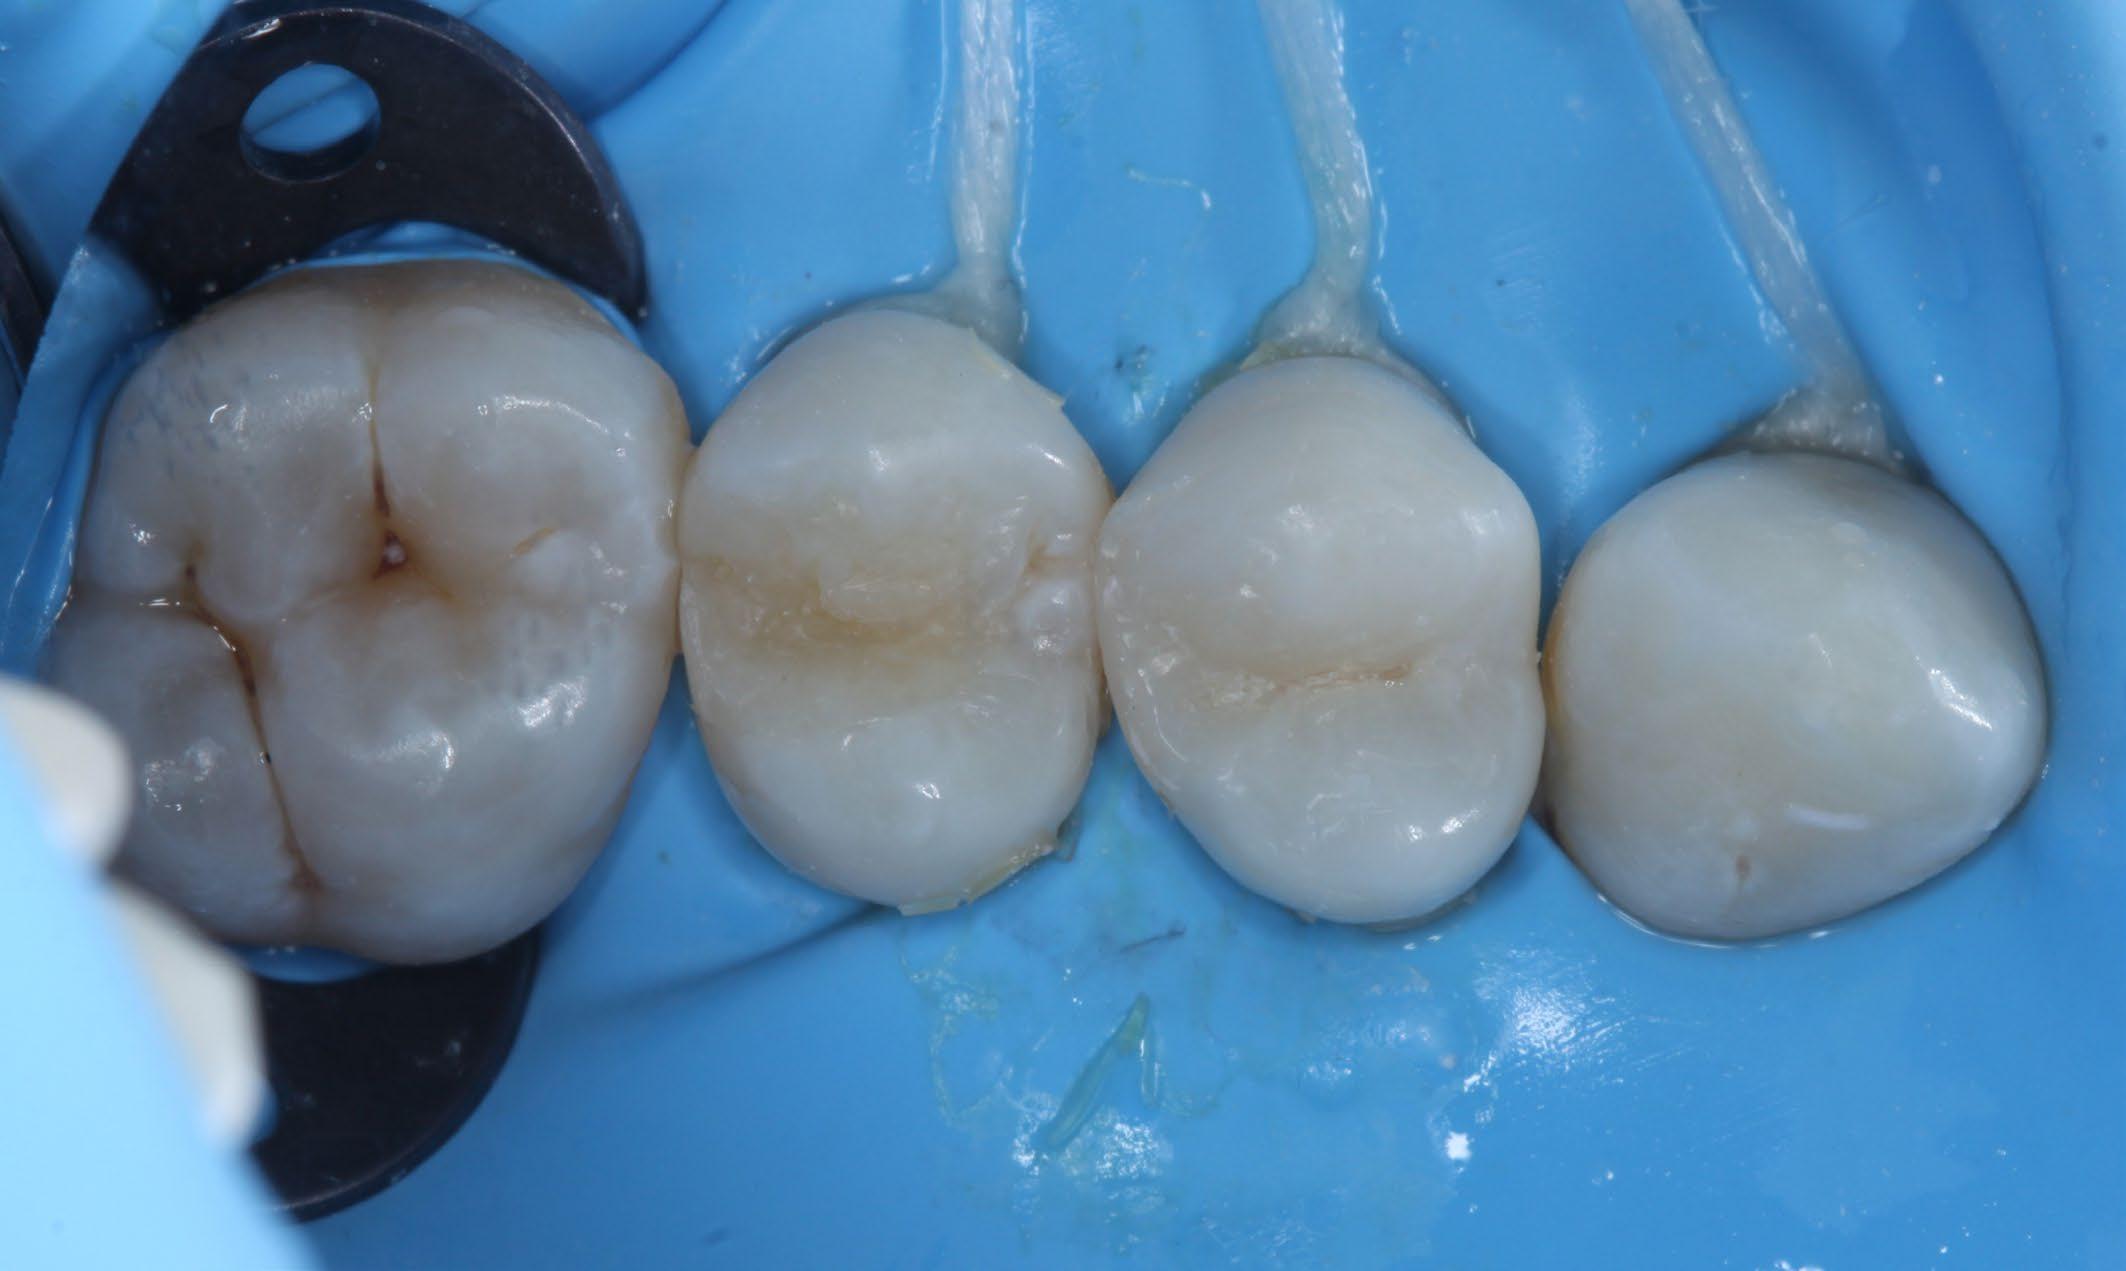

Fig. 1: Initial situation. Fig. 2: X-ray showed hidden caries at the distal side of the upper first pre-molar. Fig. 3: Isolation with rubber dam. Fig. 4: Preparation. Hidden Proximal Caries | Posterior continues next page >>>